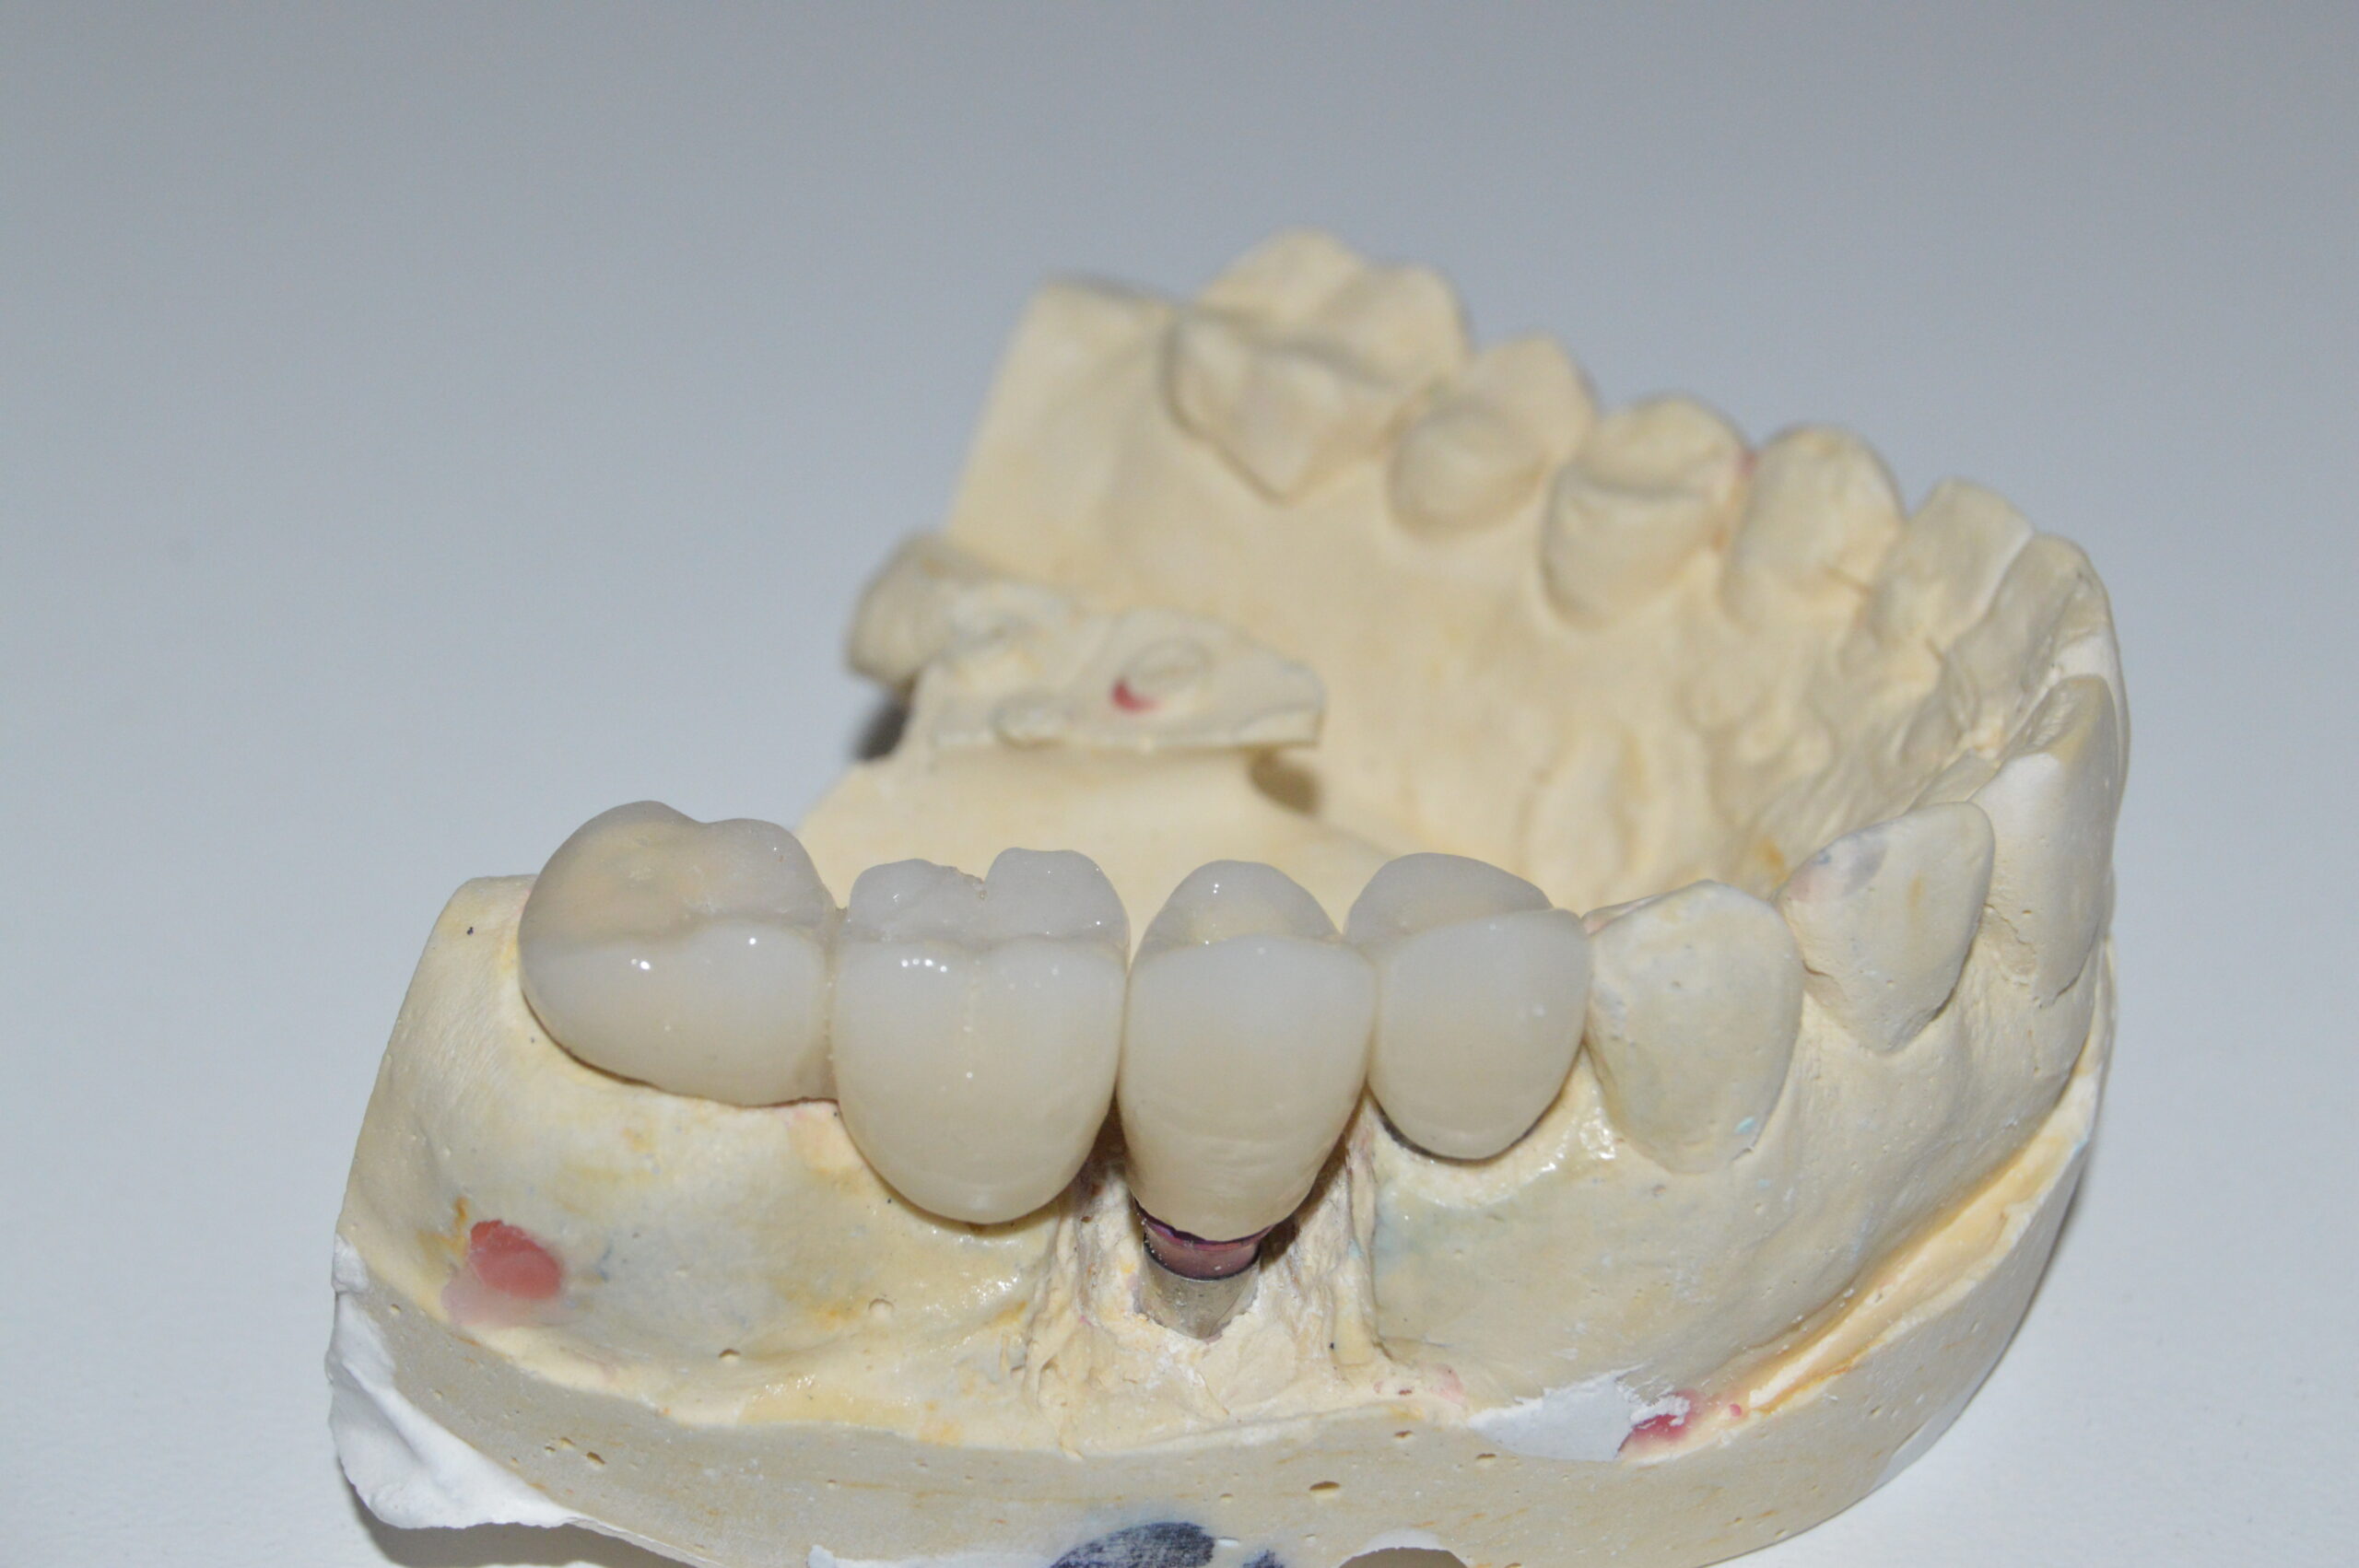

Los implantes dentales son una solución para reemplazar uno o varios dientes perdidos, consisten en un pequeño tornillo de titanio que se coloca en el hueso de la mandíbula, y luego se le une una corona dental, prótesis o un puente dental.